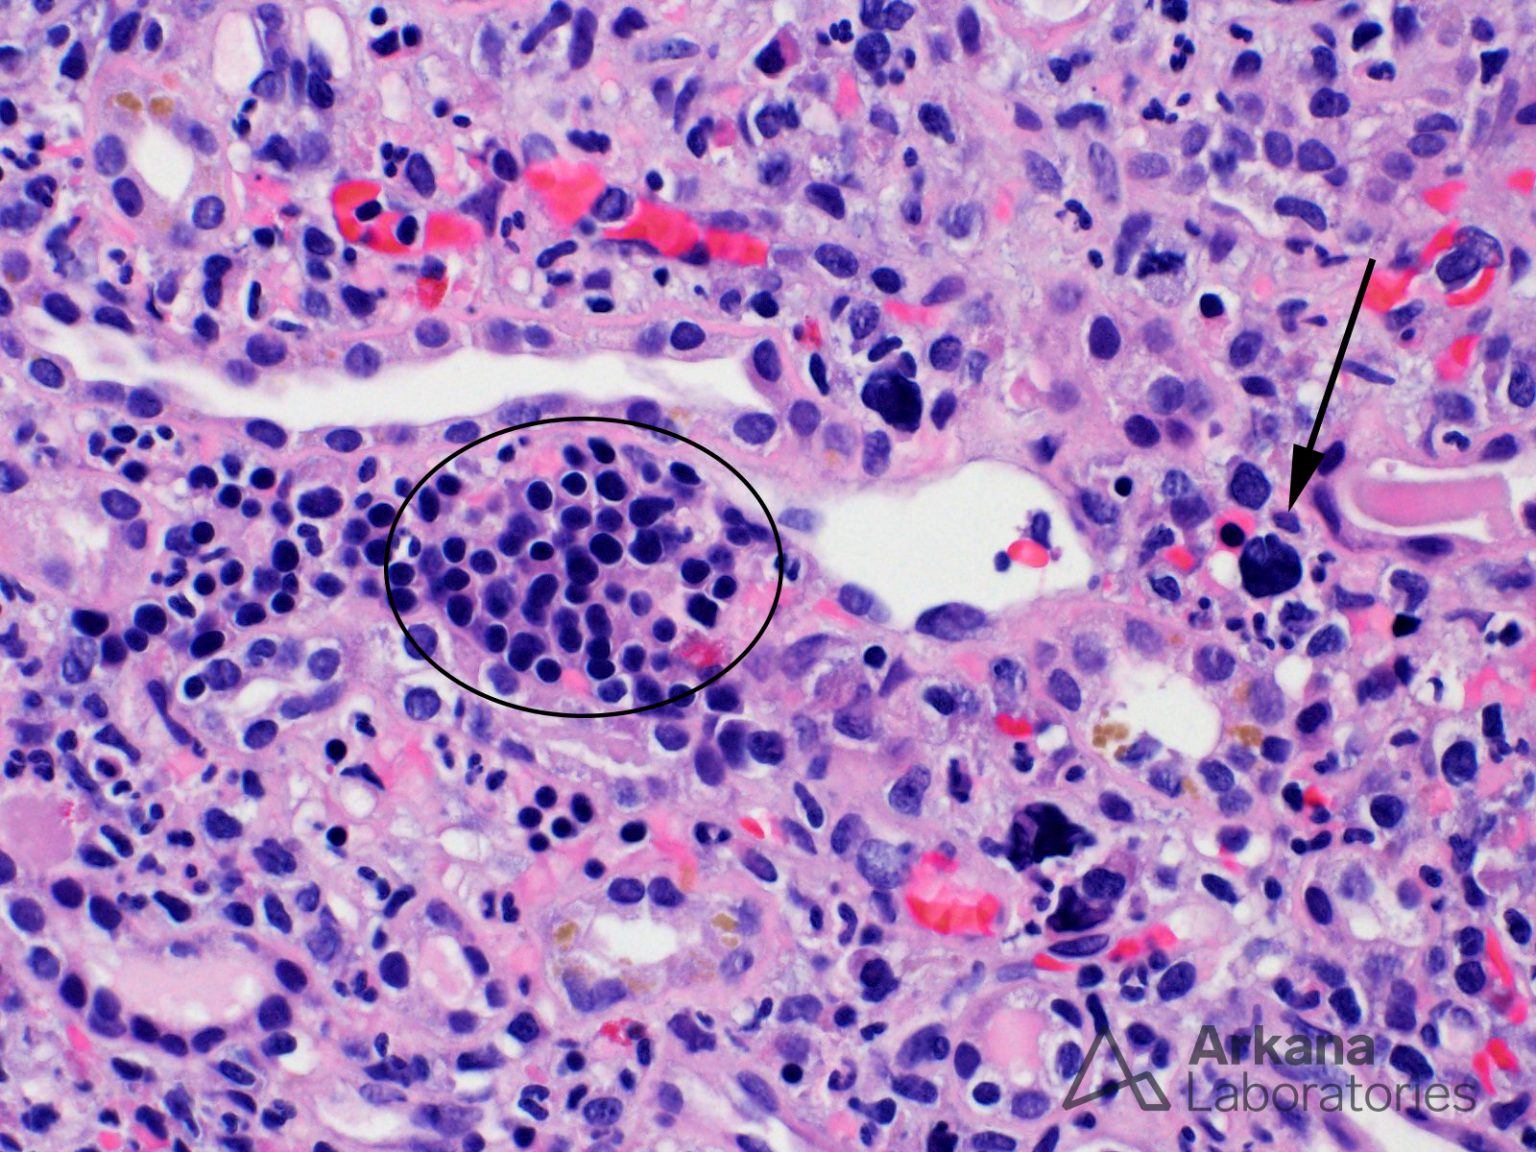

From www.arkanalabs.com

Extramedullary Hematopoiesis Teaching Points Arkana Laboratories Hematopoiesis Kidney extramedullary haematopoiesis (emh) is the development of. clonal haematopoiesis of indeterminate potential (chip) is associated with increased risk of disease, including. clonal hematopoiesis of indeterminate potential (chip) was first described in 2015 and is defined by the. extramedullary haematopoiesis (emh) is the development of haematopoietic tissue outside the bone marrow and it. Hematopoiesis Kidney.